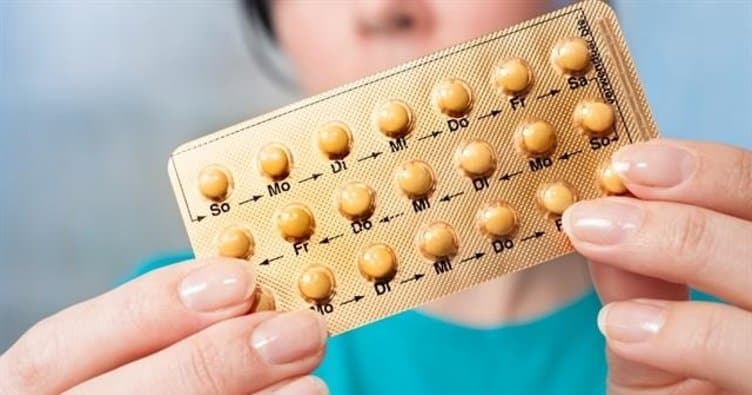

Doğum Kontrol Hapları Nasıl Kullanılır?

İstenmeyen gebeliklerin aile planlaması kapsamında önlenmesi için yaygın olarak tercih edilen yöntemlerden birisi olan doğum kontrol hapları, gerek tercih aşamasında ve gerekse kullanım aşamasında dikkat edilmesi gereken ürünlerden birisidir. Peki, doğum kontrol hapları nasıl kullanılır?

Doğum kontrol hapları nasıl kullanılır? Sorusuna cevap vermeden önce, bu hapların anlaşılır bir şekilde tanımını yapmak daha yararlı olacaktır. Hormon içeriğine sahip hapların kadının yumurtlama zamanında yumurtlamayı kısa süreliğine durdurarak istenmeyen gebeliklerin önlenmesini sağlayan ve özellikle bu amaçla üretilmiş haplara, doğum kontrol hapları denilmektedir.

- 1 paketinde 21 ile 28 hap bulunan ürünleri kullanmaya başladığınızda, paket bitene kadar günlük düzenli bir şekilde tüketmek gerekmektedir. Kutunun bitmesi halinde adet kanamasının oluşabilmesi için, yaklaşık 1 hafta ara verilmesi gerekmektedir.